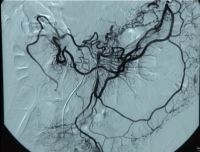

Filmbeispiel: abgangsnaher Verschluss der AMS mit Verschluss des Truncus coeliacus